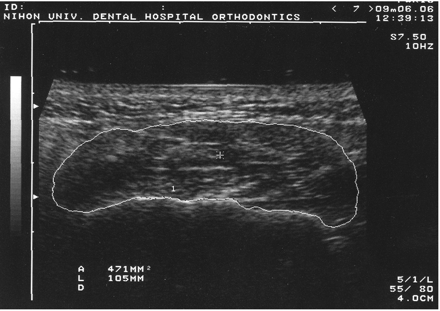

Ultrasound imaging of the masseter muscle

All images were obtained by one author (YU) using a diagnostic ultrasound system (SSA-250A; Toshiba, Tokyo, Japan) at the same visit when the radiographs were taken. This system has a real-time B-mode scanner with an annular array transducer. The specifications of the system are: piezoelectric material, polymer film P(VDF-TrFE), 7.5 MHz centre frequency, 36 mm diameter aperture, 60 mm radius of curvature, 12 elements, and 45–90 mm effective focal range. To image the masseter, the probe was placed perpendicular to the skin surface and parallel to the occlusal plane. To avoid excess pressure on the skin, the examiner’s hand was carefully placed on the occipital region. To locate the probe, the occlusal plane was drawn on the skin surface with a specially designed facebow that was placed on the tips of the upper central incisors and cusps of the upper first molars and held with a gentle bite and the operator’s hand to prevent deformation of the soft tissues. The upper and lower lips were then closed with the muscles relaxed, and the lines corresponding to the occlusal plane were drawn bilaterally on the skin surface in accordance with the outer bow. Ultrasound imaging was performed with the subject sitting, both with the muscle relaxed in the intercuspal position (CSA-relaxed) and with maximal clenching in centric occlusion (CSA-clenched). The imaging was repeated three times, during which CSA was measured by bilaterally tracing the muscle outline with the ultrasound system’s cursor (Figure 2). To ensure smoothing of the errors by margin tracing, the three measured values were averaged and the mean value was used for analysis (Table 2).

Cross-sectional ultrasound image of the masseter muscle measured using electronic cursors to instantaneously calculate the cross-sectional area.